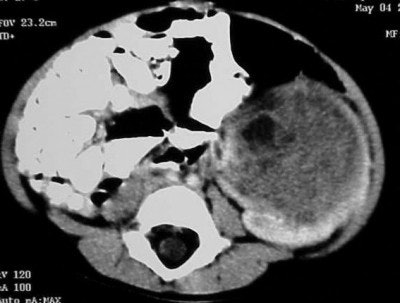

Case 1: The patient is a three-year-old black female who appears to be in no distress. The mother stated that she was giving the child a bath and noticed that her abdomen looked distended, and harder on the left side than the right. All the child’s labs are normal, and there is no family history of medical problems.

Axial images (Figures CT 10 and CT 11) show a mass beginning just below the kidneys on the left side and extending almost through the pelvis. The child was diagnosed with Wilm’s tumor of the left kidney.